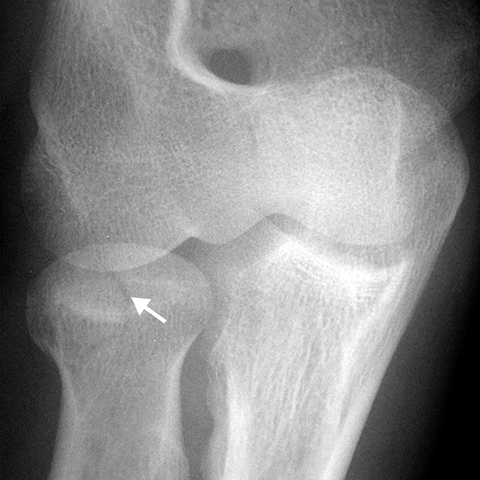

Radial Head fracture